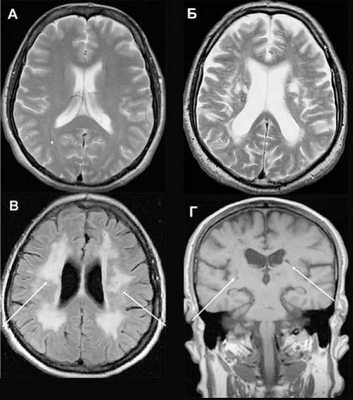

Томограммы множественной деменции

Сосудистая деменция (ишемические очаги)

- МРТ головного мозга. Томографическая картина неспецифична. Церебральная атрофия носит диффузный характер, крайне вариабельна, менее выражена, чем при деменции альцгеймеровского типа. Типичны диссоциирующие с клинической картиной незначительные изменения затылочной коры. Поражение подкорковых ганглиев практически тотальное. С целью исключения сосудистого генеза слабоумия исследование дополняется проведением МРТ церебральных сосудов.

- ПЭТ-КТ головного мозга. Определяет снижение нейрометаболизма и перфузии в затылочных долях, выраженное поражение подкорковых структур. Определяющее диагностическое значение имеет диссоциация слабой затылочной атрофии по данным МРТ с выраженными дисметаболическими процессами этой области по результатам ПЭТ.